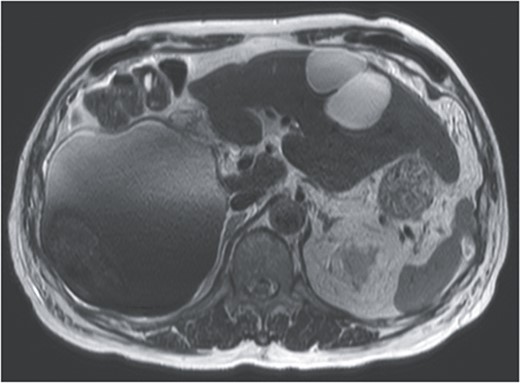

On referral to our hospital, his vital signs were within normal limits. The abdominal examination revealed rebound tenderness in his right upper quadrant region. There was no abdominal distension. The initial laboratory tests demonstrated a normal hemoglobin (10.2 g/dl) and elevated C-reactive protein levels (9.6 mg/dl). The results of serum tumor markers were as the follows: CA19-9, 193 784.3 U/ml; carbohydrate antigen 125 (CA125), 91.6 U/ml; carcinoembryonic antigen (CEA), 2.1 ng/ml; α-fetoprotein (AFP), 3.0 ng/ml; des-γ-carboxy prothrombin (DCP), 19 mAU/ml (Table 1). Dynamic CT showed a large cystic lesion (17 cm × 14 cm × 12 cm) in the right liver and discontinuation of the cystic wall and retention of ascites mainly the right subphrenic region (Fig. 1). T2-weighted single shot turbo spin echo magnetic resonance imaging (MRI) showed a-low intensity region with dorsal predominance in the high-intensity area and fluid–fluid level (Fig. 2). Gadoxetic acid (Gd-EOB) enhanced MRI didn’t show any lesion suggesting mural nodule in the cystic wall in any phase (Fig. 3). Paracentesis showed bloody fluid and the tumor marker levels in the sampled ascites were as the follows: CA19-9, 2 672 400.0 U/ml; CA125, 2618.9 U/ml; CEA, 41.7 ng/ml; AFP, 1.4 ng/ml; and DCP, 10 mAU/ml (Table 1). Cytology of the ascites showed no findings of malignancy.

Gadoxetic acid (EOB) enhanced MRI didn’t show contrast effect with a cystic lesion in any phase.